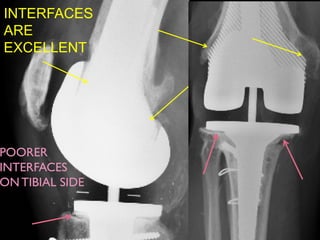

A HUGE CAVITY BUT A GOOD SOLUTION

7YRS POST-OP :

GREAT ONTHE FEMORAL SIDE

INTERFACES

ARE

EXCELLENT

POORER

ON TIBIAL SIDE

7YRS POST-OP : GREATONTHE FEMORAL SIDE

A HUGE CAVITYBUT A GOOD SOLUTION